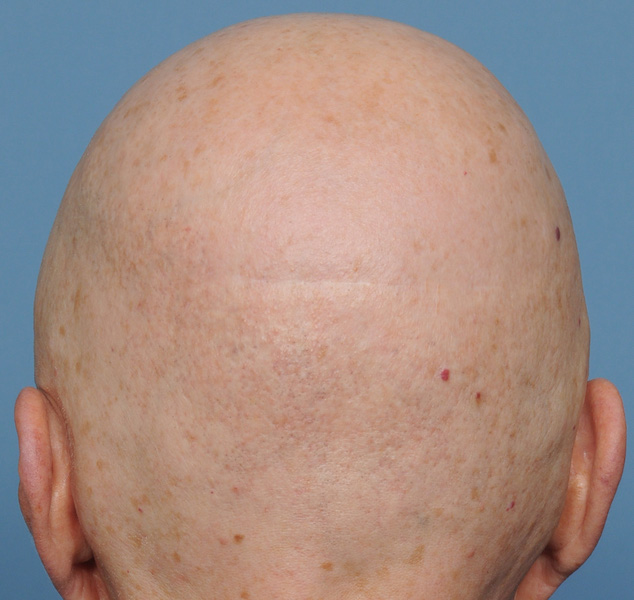

Patient 100

Desire for reshaping of an asymmetric flat back of the head in a shaved head male.

A combined back of the head reshaping procedure was done with a custom skull implant, sagittal ridge reduction and a right temporal muscle reduction.

Desire for reshaping of an asymmetric flat back of the head in a shaved head male.

A combined back of the head reshaping procedure was done with a custom skull implant, sagittal ridge reduction and a right temporal muscle reduction.